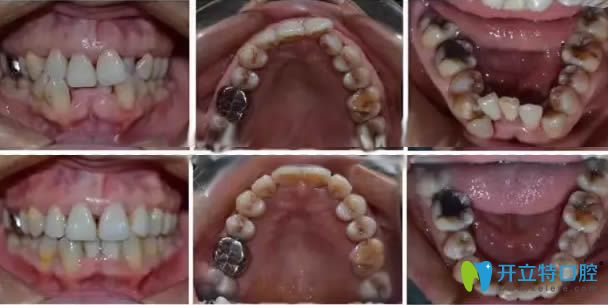

顧客:王姐,43歲,整牙一直是她的心愿,早年因?yàn)樽錾饷€要照顧孩子,所以一直拖著,現(xiàn)在孩子大了,是時(shí)候給牙齒做個(gè)美好的改變了;

口腔癥狀:牙列不齊擁擠、齲齒、牙齦炎癥;

主治醫(yī)師:杜如;

治療方案:齲齒治療后,拔牙+時(shí)代天使隱形牙套矯正;

治療效果:王姐嚴(yán)格按照醫(yī)囑認(rèn)真佩戴隱形矯正器,多次定期復(fù)診,一年半后終于成功結(jié)束了矯正。43歲的王姐,在牙齒矯正行列中屬于是年紀(jì)偏大的,但并不影響后期矯治的效果。從圖片可以看出來,矯正的效果非常成功,張姐本人也表示非常滿意。